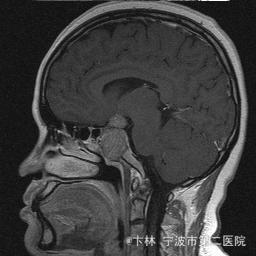

40岁女性,因“双眼视力下降三月余伴停经1个月余”入院。 患者三月前无明显诱因下出现双眼视力下降,视物模糊,尤以左眼为甚,只能近距离看到手动,无头痛、头晕,无恶心、呕吐,无视物旋转,无行走困难等不适,患者曾在某眼科医院就诊治疗,考虑为双眼视神经炎,予以营养,补液对症等治疗(具体不详),情况不见好转,近一月来患者月经停止,来我院神经外科门诊,予以查头颅CT,头颅MRI,提示“垂体大腺瘤”,为求进一步治疗收住入院

予以完善血,尿,粪常规检查,及凝血功能全套,输血功能全套及垂体功能全套,蝶鞍冠状CT等术前检查措施,行经蝶入路垂体瘤切除术。术后予以对症,补液,调节血电解质等治疗,患者视力明显改善,复查头颅MRI提示肿瘤基本全切,一周后患者出院。

此病人颅内垂体瘤体积较大,突破鞍隔压迫视交叉,故患者视力视野障碍为首发症状,该肿瘤主体有大部分向蝶窦腔生长,因此采用经蝶手术入路,肿瘤切除满意,术后患者视力视野恢复满意,。